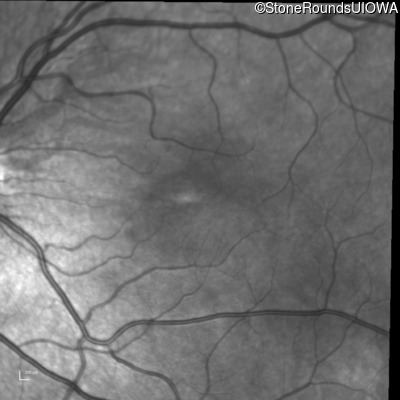

Infrared Fundus Photograph - Right - 20/50

Exemplar